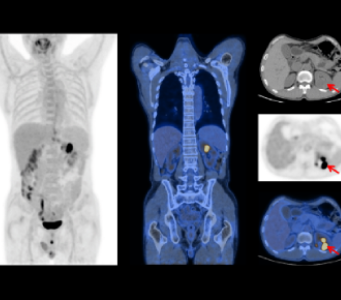

8 minutes Whole-body Scan

2.2mm small Lesion detection